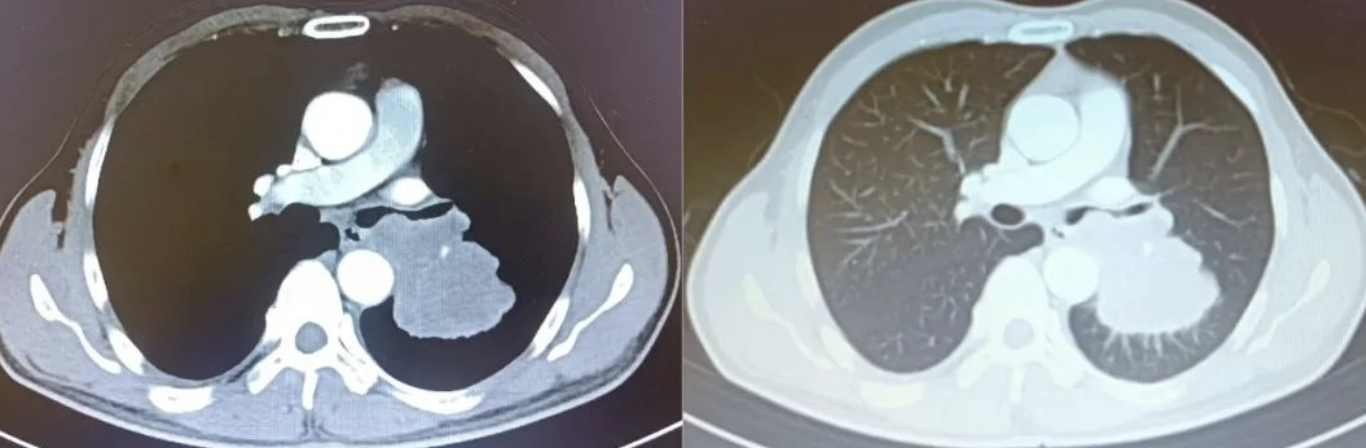

,严重影响了日常生活。于是,陈大哥在家人的陪同下,来到了漳州第三医院呼吸与危重症医学科门诊就诊。经过胸部CT检查,陈大哥的

入院后,医院立即安排支气管镜检查,发现陈大哥出现呼吸困难是由于重肿瘤组织阻塞导致的。若不进一步处理,随着肿瘤体积增大,很快就会出现左主支气管完全阻塞,加重呼吸困难的情况。

面对陈大哥复杂的病情,当务之急就是快速解除狭窄、通畅气道。经过呼吸与危重症医学科黄若新主任团队的研究讨论,决定在内镜下进行活检。随后的病理报告显示:(肺组织)非小细胞肺癌,结合免疫组化检查结果,符合鳞状细胞癌。

陈大哥经对症治疗后,狭窄好转。为了更好地缓解陈大哥呼吸困难的症状,黄若新主任再次组织肿瘤内科、胸外科等科室进行多学科会诊。最终认为陈大哥左肺鳞癌(ⅢC期)诊断明确,目前无外科手术指征,而行硬质支气管镜下左主支气管金属覆膜支架植入术,是目前最佳的治疗办法,其创伤小、效果好,能够快速解决气道狭窄的问题。在与患者家属仔细沟通后,患者同意行支架植入术。